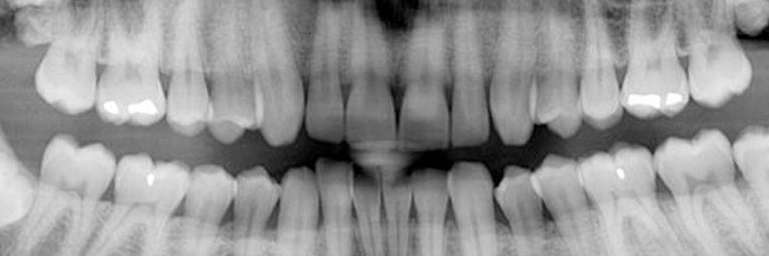

This scan can be used in conjunction with other dental x-rays taken of your teeth. The CBCT scan differs from traditional x-rays primarily in its ability to display a 3D image instead of the traditional 2D images captured previously. This aspect is very beneficial for clinicians when planning implants, root canals, and diagnosing/evaluating areas of concern for patients.

Getting a CBCT is fast and comfortable. You have probably had a PANOREX or PANORAMIC image taken before at your dental office, where you stand/sit while the scanner rotates around your head. This is essentially the same experience.